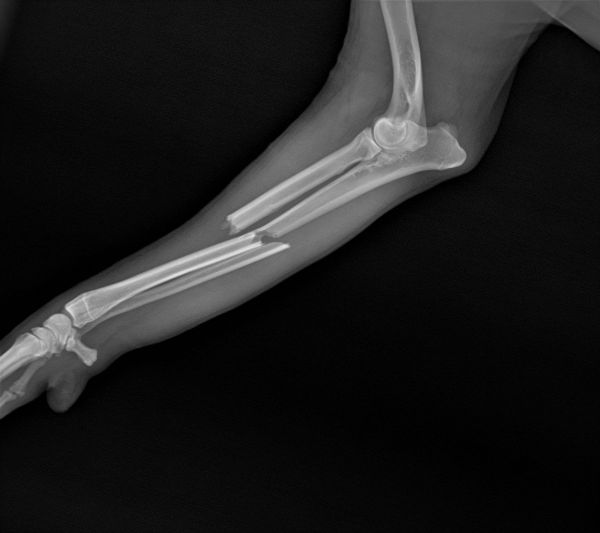

猫的骨骼整体还是比较大的,所以多数腿骨的骨折会选择内固定的方法,关节和腿骨骨裂则首选外固定,做好对接后,上夹板绑定。人古话说伤筋动骨100天,宠物其实也差不多了,猫狗的愈合速度相对快也需要45-80天的时间,根据骨折的位置和严重程度不同,恢复时间也有很大差别。

2周前上班路上,前面一辆电动自行车带着一只狗,在躲避行人的时候车猛的拐弯,车倾斜的时候狗顺势下地,后车轮从狗腿上碾过,瞬时血肉模糊。立刻用衣服铺在地上,给狗放在羽绒服上整体托起,赶快送到医院X光检查,一条腿只是表皮蹭掉一块肉,另外一条腿尺骨骨裂,颈椎和脊椎没有明显的骨裂。因为没有彻底断裂,所以没有做内固定,在外面用夹板固定,随后对皮肉伤进行消炎治疗。经过1周后精神和食欲才逐步恢复,狗狗尝试站起走路,排除脊椎受损可能,慢慢走出惊吓的阴影,这如果压过的是脖子或者脊椎,面临的可能就是后半生的瘫痪了。